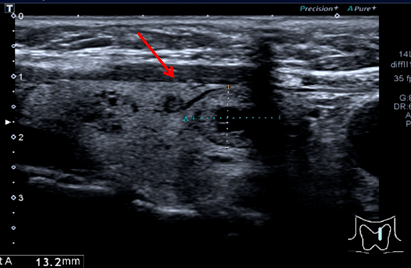

结节内可见点状强回声,边界欠清,形态欠规则。(TIRADS分类:4a类)